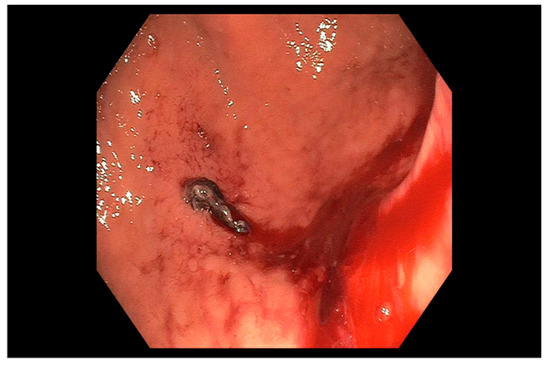

Role of Endoscopy in Lower Gastrointestinal Bleeding